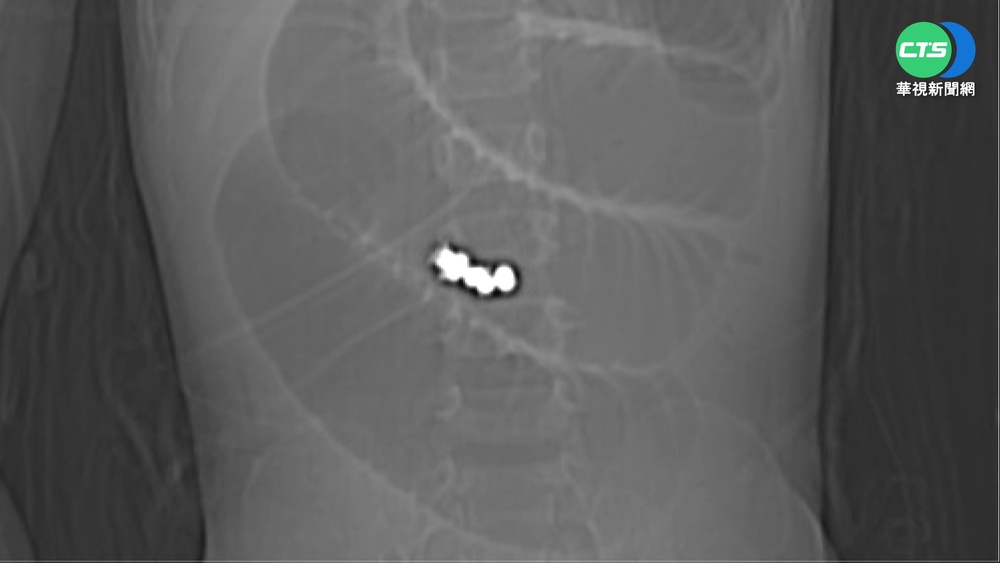

1歲童嘔吐就醫 腸胃驚見8顆巴克球

3歲童一夜狂吐 X光驚見「巴克球」已致腸穿孔...

兒童玩具21%不合格 巴克球誤吞恐致腸穿孔

一歲童嘔吐就醫 腸胃道驚見巴克球!

男童嘔吐急就醫 腸道X光驚見「巴克球」

男童誤吞"巴克球" 腸穿孔險死

【晚間搶先報】男童誤吞"巴克球" 腸穿孔險死

巴克球磁力相吸! 幼兒誤食腸穿孔